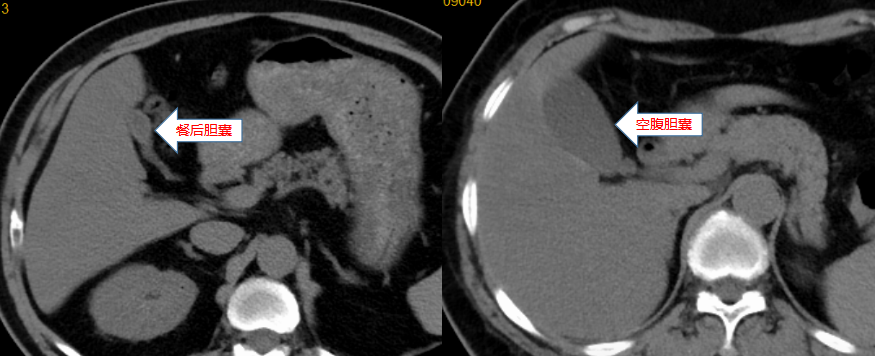

腹部CT检查前,通常需要患者空腹4-6小时以上。这是因为一旦进食,胆囊就会排空胆汁,对食物进行消化,导致胆囊充盈度不高,不利于观察病变情况,而空腹情况下能使胆囊充盈,让病变一目了然。此外,胃肠道里内存在积食也容易引起伪影,影响图像诊断的准确性。